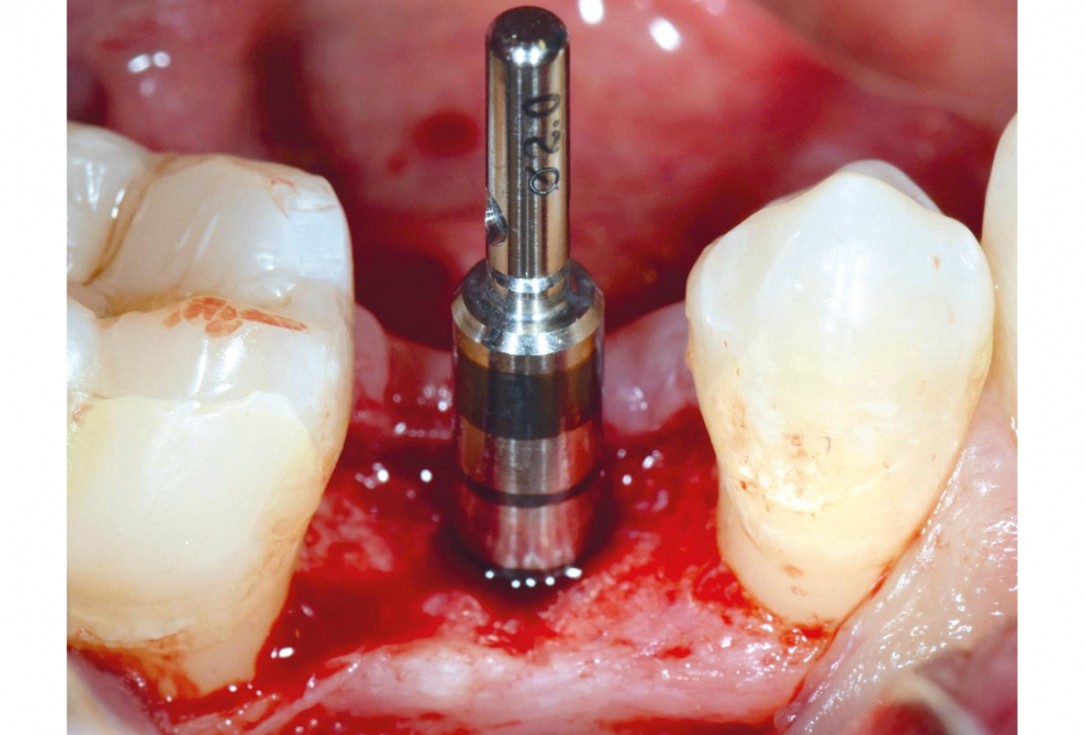

9/17 - Implant placementApplication of mucoderm® for soft tissue management around single implants at second stage surgery Dr. C. De Annuntiis